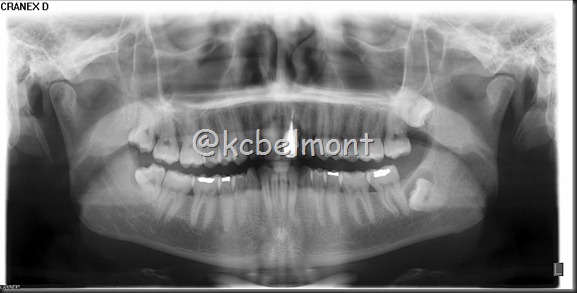

Imagem Radiográfica da Semana (36)

Radiografia panorâmica (CIR - Centro da Imagem Radiográfica)

Neste Imagem Radiográfica da Semana, temos uma radiografia panorâmica, onde o elemento 38 encontra-se incluso, mésioangulado, impactado. Mas, envolvendo a coroa do mesmo temos imagem radiolúcida, envolta por halo radiopaco, caracterizando uma rarefação óssea de aspecto cístico, sugerindo cisto dentígero. O que poderá ser confirmado através de biópsia.